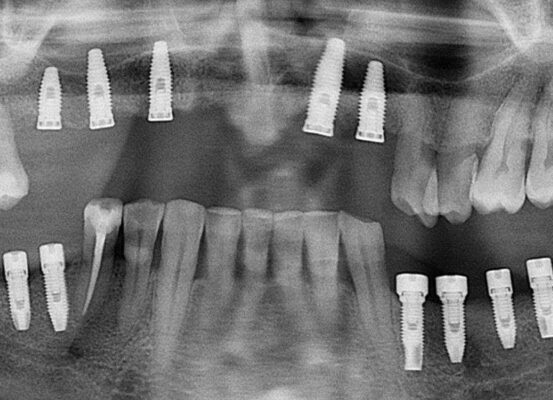

Paciente de 90 años operado para instalación de 2 implantes en el sector anterior con injerto óseo.

Les comparto el caso de un paciente de 90 años operado para instalación de 2 implantes en el sector anterior con injerto óseo.Con esto me gustaría reforzar 3 cosas.1- No hay edad para sonreír.2- Un pa